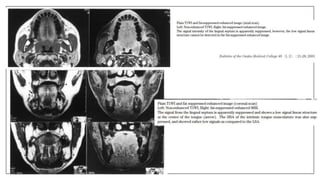

Normal anatomy

Pathologies